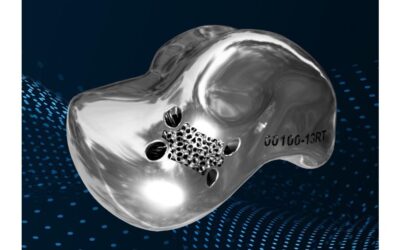

Patient-specific Talus Replacement

The restor3d Total Talus Replacement implant is a 3D-printed and polished implant designed and made individually for each patient using data from computed tomography (CT) scan. The implant is intended to reduce pain, increase physical function, and maintain range of...